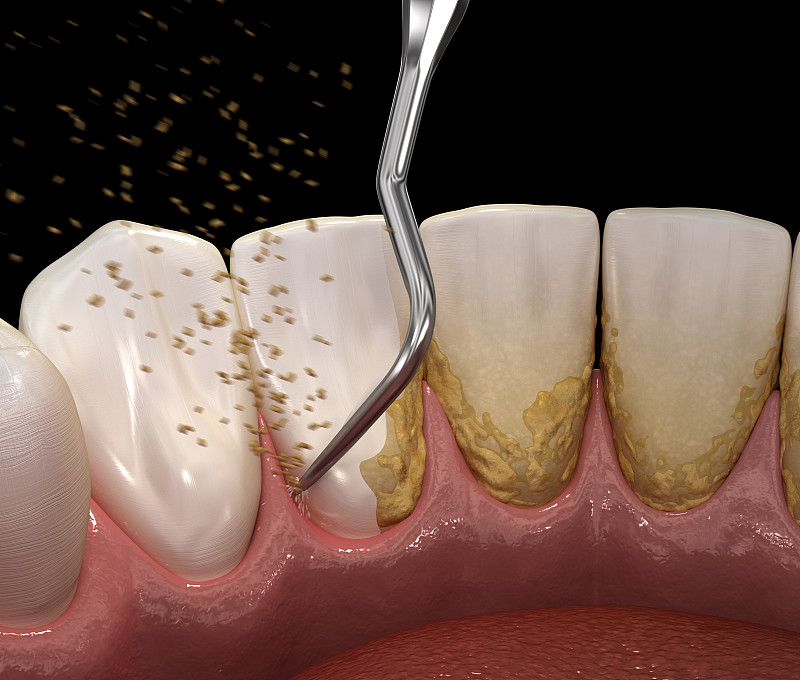

龋齿详情